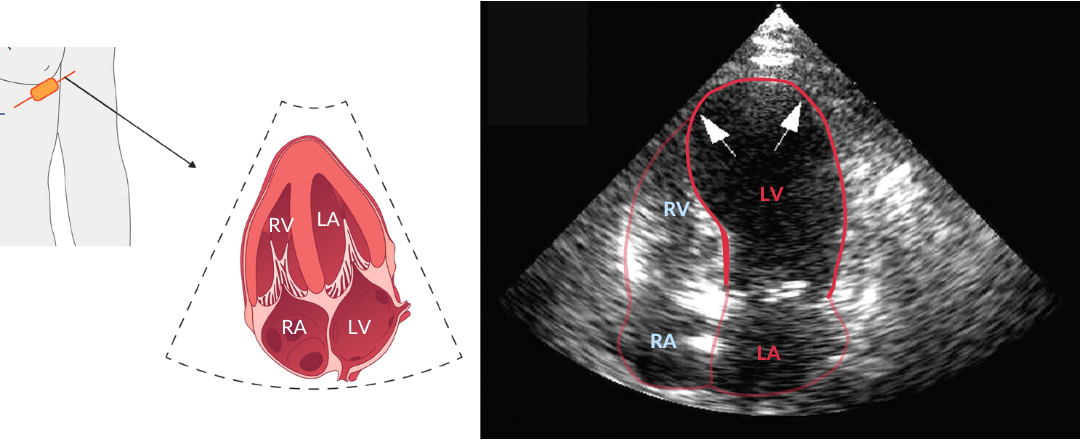

Tijdens de klinische opname wordt er ook een echocardiogram vervaardigd. Hieronder zie je een apicaal vierkameraanzicht van het hart. Dit is gemarkeerd; LV = linkerventrikel; LA = linkeratrium; RV = rechterventrikel; RA = rechteratrium. Het valt op dat de apex en middensegmenten van het linkerventrikel gedilateerd zijn. Ook is er sprake van hypokinesie apicaal en mid-ventriculair (niet zichtbaar op deze statische plaatjes).